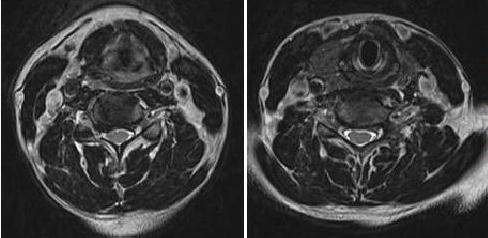

The patient has an isolated axillary nerve injury. This is a well recognized, though relatively infrequent, complication of shoulder dislocation. A diffuse plexus injury is ruled out by the evidence of motor and sensory preservation in other upper extremity muscles. The presence of shoulder external rotatory function rules out both C5 nerve root injury and suprascapular injury.